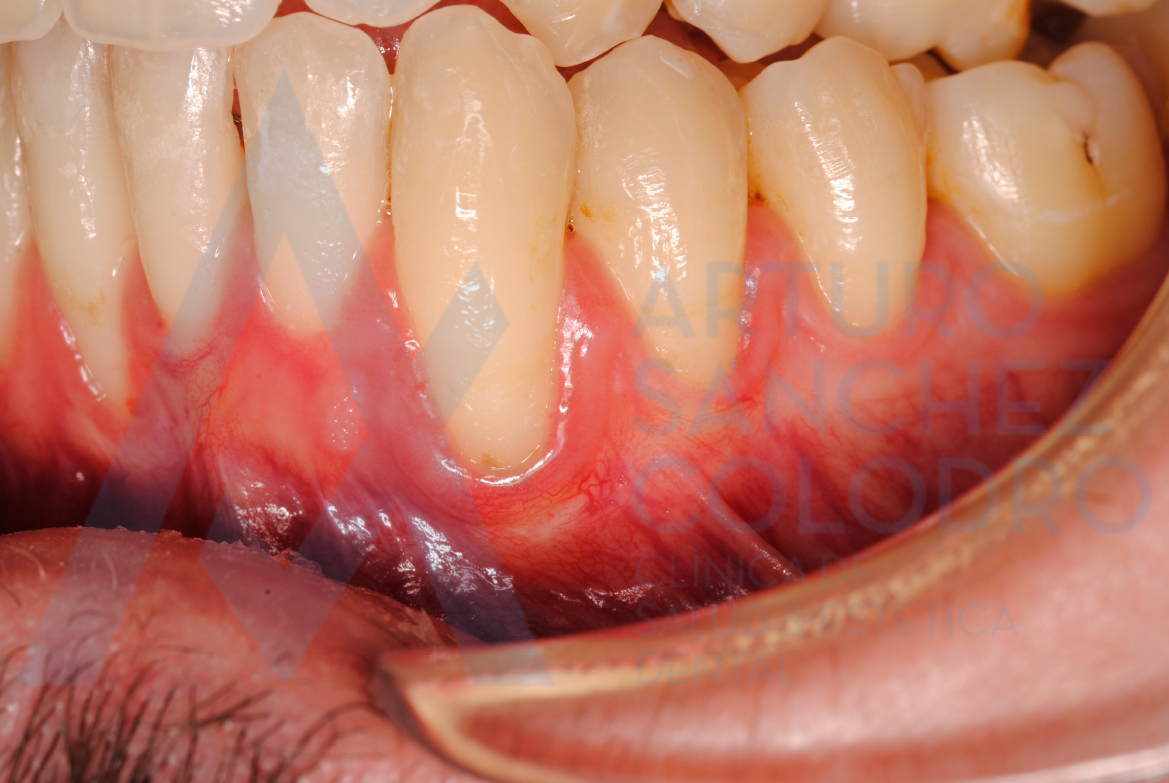

Estas son las imágenes obtenidas de exploración intraoral inicial: